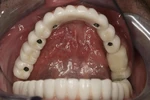

التهاب ما حول الزرعة السنية (بيري إمبلانتاتيتيس)

التهاب مخاطية الغشاء المخاطي حول الزرعة (بيري-إمبلانت مخاطيتيس)